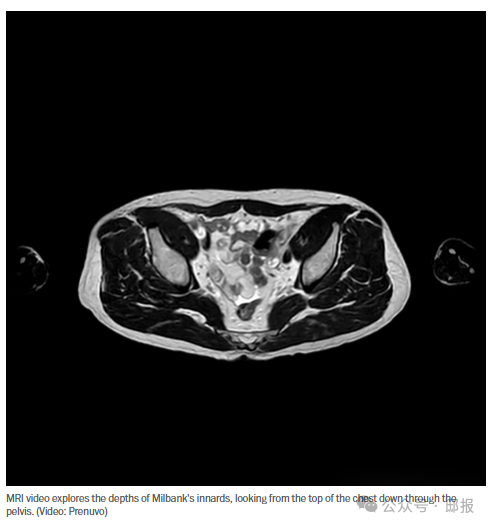

和许多新兴技术一样,这项技术既能改善我们的生活,也能让我们痛苦不堪,或者两者兼而有之。目前尚无人知晓最终结果如何。 十个医生中有九个同意:我是一个极富创造力的疑病症患者。 凭借从网上搜集的医学知识,我成功地给自己误诊了多种疾病,其中包括:心脏病、胰腺炎、肝肾疾病、血小板减少症、结肠癌和前列腺癌、莱姆病以及记忆力衰退(虽然我记不清具体是什么时候发生的)。侧睡时偶尔的疼痛?一定是癌症。剧烈运动后的头痛?一定是脑动脉瘤。我的墓碑上会刻着:“我早就告诉过你了。” 所以,几年前当我第一次听到那些长寿专家吹捧全身核磁共振扫描时,我自然而然地就准备报名了。这可是个从大脑到跖骨检查全身,甚至能找到小至2毫米的异常点的绝佳机会。我再也不用凭空想象自己有什么毛病了。现在我可以安心地告诉自己我很健康——或者毫无疑问地证明自己病入膏肓。 但事情比这复杂得多,无论是像我这样爱操心的健康人,还是其他许多不擅长自我误诊的人。 驱动这些全身 MRI 的新技术——一种叫做扩散加权成像(别问我怎么解释)的技术,结合人工智能的模式识别——有可能通过在癌症初期、无症状动脉瘤和其他隐藏的潜在杀手变得致命之前将其发现,从而拯救我们的生命。 但每次扫描费用高达2500美元,而且保险公司不予报销。更糟糕的是,核磁共振成像每发现一例癌症,就会产生略多一些的假阳性结果,这些假阳性结果需要进行活检,而活检可能会带来感染、出血和精神痛苦的风险。即使扫描没有产生假阳性结果,也几乎总会发现一些模糊且令人不安的异常情况。 和许多新兴技术一样,这项技术既能改善我们的生活,也能让我们痛苦不堪,或者两者兼而有之。目前尚无人知晓结果如何,因为我们是第一批能够如此清晰地审视自身内部构造的人类。观察过自己的身体内部之后,我们会感觉更好吗?还是会开始为一些我们以前从未想过要担心的事情而焦虑不安? 生活的一部分乐趣在于未知,在于对明天的未知。如今,由于先进的成像技术、基因组测序和其他革命性的筛查工具, 我们或许能够预测未来,或者至少给人一种预测未来的错觉。但我们真的想要这样吗? 美国放射学会表示我们并不支持这种做法。该学会2023年发布的声明至今仍然有效,声明指出目前尚无“充分证据”支持进行全身筛查,并警告称,这种扫描可能会导致不必要的检查和费用。 但美国放射学会(ACR)质量与安全委员会主席大卫·拉尔森告诉我,随着更多数据的出现,情况可能会有所改变。“当人们问我‘你会推荐吗?’时,我会说这取决于你对不确定性的容忍度,”他举例说,比如有人被发现患有临界性主动脉瘤,医生建议他等待观察。“如果这不会让你夜不能寐,那么我未必会反对。” 我问他是否认为全身磁共振成像会在医学领域普及。“就我个人而言,我认为会的,”他说。“从人类历史的长河来看,我们至少已经存在了几千年,而这种级别的成像技术才出现几年而已……我们只是恰好处于技术前沿。” 我那位长期以来一直耐心倾听我各种臆想病症的家庭医生,起初并不赞成我做核磁共振检查。但在我上次复诊时,他改变了主意,因为核磁共振扫描结果已经为他的几位病人带来了救命的发现。 于是我决定放手一搏。结果让我庆幸自己做了这个决定。 亲爱的读者,我没有什么需要对您隐瞒的,所以我在这篇专栏文章中附上了我的内脏照片。其他记者或许会高谈阔论透明度,但他们当中又有多少人向您展示过自己脾脏的视频呢? 我抵达位于马里兰州贝塞斯达的Prenuvo诊所时,接待员询问我想要穿多大尺码的手术服,以及在检查期间想听什么Netflix剧集。候诊室的小吃吧提供冰沙、意式浓缩咖啡和各种小吃。洗手间里有漱口水包,卫生纸卷上贴着印有“P”字样的金色贴纸,代表Prenuvo。 感觉更像是酒店业而不是医疗业,这也不难理解:顾客是自费的,而作为最大的全身 MRI 公司,Prenuvo 希望他们能享受到水疗体验——或者说,在周围强大的磁铁叮当作响的情况下,尽可能地享受到水疗体验。 预约扫描时间前十分钟,我被领进更衣室,柔和的米色墙壁上装饰着抽象艺术作品。我穿上炭灰色手术服和一次性鞋套,浏览着书架上的读物,书名诸如《科学健康时代》。 接下来,我去了核磁共振舱,那是两台形似宇宙飞船的机器,位于相邻的房间里,灯光昏暗。我躺在平台上,技术人员给我戴上耳机(耳机里播放着默认的SPA音乐)和射频电极片,用来引导核磁共振扫描。然后他把我推进“宇宙飞船”里,接下来的半个小时里,我只能听从一个机械女声的指令,这个女声盖过了敲击声和砰砰声:“吸气。呼气。屏住呼吸。你可以再次呼吸了。” 虽然比不上峡谷牧场(Canyon Ranch)那种恐怖体验——那个管子里空间狭小,越来越热,我的头骨也感觉到了强烈的震动——但也算不上什么折磨。整个过程没有辐射,也没有注射造影剂。 之后,我换了身衣服,从小吃店买了些薯片和一瓶Spindrift饮料,然后出门去躲避威斯康星大道上飞驰的车流。我想到可能会出现的讽刺意味十足的新闻标题:行人离开长寿诊所时被撞身亡。我们或许希望科技能给我们带来渴望已久的确定性,但生活本身,并将永远,充满变数。 然而,有一件事是肯定的:我得等一到两周才能拿到结果。Prenuvo公司预防医学高级医疗总监维卡什·莫迪曾提醒说:“这段时间,一些患者的焦虑情绪会达到顶峰。”但如果放射科医生发现“高度异常”的情况——比如巨大的、难看的癌症之类的——我会在几天内接到电话。 大约每20人中就有1人会接到那个令人恐惧的电话。Prenuvo公司今年早些时候发布的一项针对1011名参与者的研究发现,4.9%的扫描结果需要进行后续活检。其中,2.2%确诊为癌症,其余2.7%为假阳性。在扫描发现的22例癌症中,86%的患者没有任何特定症状。 但如果说发现真正严重的问题很少见,那么发现异常几乎是必然的。莫迪表示,只有五分之一的扫描结果完全正常。绝大多数患者最终都处于一种模棱两可的状态,虽然可能存在一些可疑之处,但并不需要紧急跟进。 我当时觉得我可以接受这种不确定性。更大的障碍是价格。只要保险不涵盖全身核磁共振,这项检查就只能是富人(迄今为止,已有13万例普瑞努沃注射治疗,其中金·卡戴珊称之为“救命”的)以及其他能够凑齐2500美元进行全身检查或4000至4500美元进行包含血液检查的“增强筛查”的人才能负担得起的。我的老板提醒我,这次检查不能用我的报销单。 所以我选择了价值1000美元的躯干扫描——虽然仍然很奢侈,但对更多人来说还是可以负担的。而且,它的性价比最高。“这是我们的强项,”莫迪说道,并指出在Prenuvo研究中检测到的22例癌症中,有17例位于胸部、腹部或盆腔。莫迪说,他们经常在这些部位发现一些癌症,而这些癌症往往要等到无法治愈才会被发现,比如“那些可怕的胰腺癌”。 扫描后的头几天过去了,没有接到任何坏消息电话。核磁共振检查六天后,一位“高级专员”发邮件给我安排咨询,又过了六天,我收到通知说我的报告已经准备好了。 我忐忑不安地登录系统,发现……我的身体有很多问题,其中最令人担忧的是“右下肺叶有一个2.5毫米的肺结节”和“胰尾部有一个4.6毫米的导管内乳头状黏液性肿瘤”。总共,扫描结果发现了12处异常。 肺癌和胰腺癌?我完了! 不完全是这样。12项检查结果中有10项被评为“轻微”,其中6项是肌肉骨骼磨损问题,我之前就因为常见的疼痛而有所察觉。即使是那两项“中度”检查结果,读完之后也感觉没那么糟糕。肺部的“未定病变”无需后续检查,而胰腺的病变则属于“低风险”。 除了书面报告外,还有一大堆扫描照片和视频,看起来像是炖牛膝和肋眼牛排的切片。其中有一段红色波浪线状的“肿瘤检测”序列;一个黑蓝色的旋转躯干;一段看起来像变形虫的“脂肪敏感序列”;各种显示器官、肌肉和骨骼溶解和重新出现的视频;以及一段显示我的胰腺像风向标一样旋转的视频。